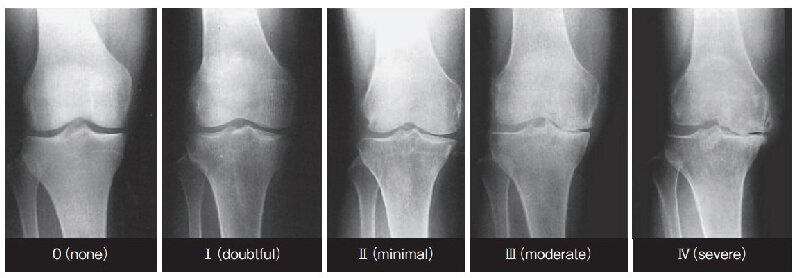

- 0:正常

- Ⅰ:関節裂隙狭小のないわずかの骨棘形成、または軟骨下骨硬化

- Ⅱ:関節裂隙狭小(25%以下)あるも骨変化なし

- Ⅲ:関節狭小(50%〜75%)と骨棘形成、骨硬化像

- Ⅳ:骨変化が著しく、関節裂隙狭小(75%以上)を伴う

Kellgren-Laurence分類(変形性膝関節症のgrade分類)